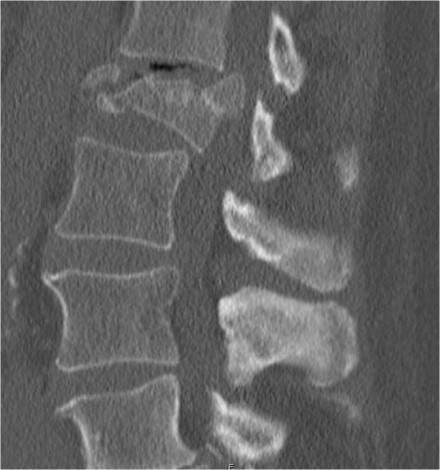

The images show a compression fracture.

All we see is a cortical disruption in the upper anterior wall of the vertebral body and slight loss of height ventrally.

The posterior vertebral cortex is intact.

The sagittal reformatted image also shows the cortical disruption.

Notice that on a 2.5mm axial slice you can miss these fractures.

You have to look at the thin slices to detect such a subtle fracture.